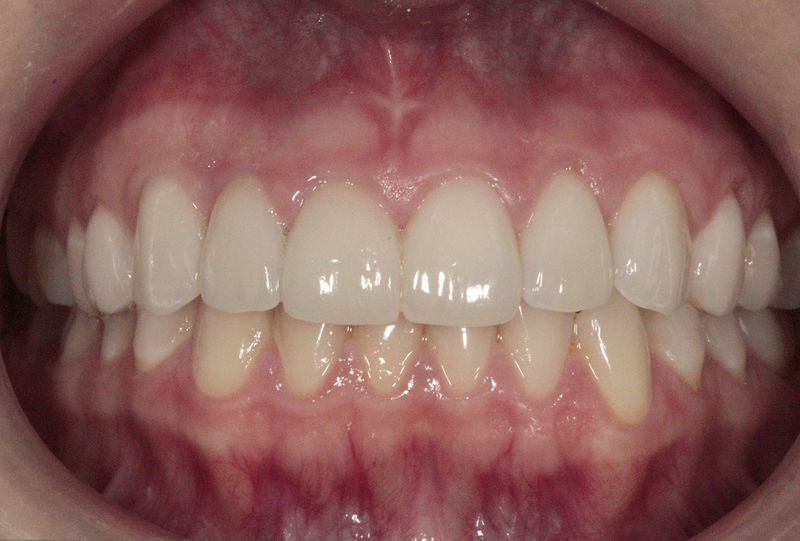

Amplia gama de tratamientos para mejorar la apariencia de la sonrisa, corrigiendo el color, la forma, el tamaño, la alineación y la posición de los dientes. Los procedimientos más comunes y solicitados incluyen el blanqueamiento dental, las carillas y coronas, así como las resinas.

Son restauraciones que cubren toda la cara frontal del diente, generalmente empleadas en el sector anterior y cuya finalidad es primariamente estética.

Restauraciones fabricadas en el laboratorio con materiales estéticos, los cuales cubren de manera total dientes anteriores y posteriores. Se utilizan primariamente para restaurar dientes con caries, fracturas y/o defectos amplios, así como soportes de puentes. Para poder enviar el caso al laboratorio se toman impresiones utilizando materiales de impresión o técnicas modernas digitales.

Ortodoncia y coronas.